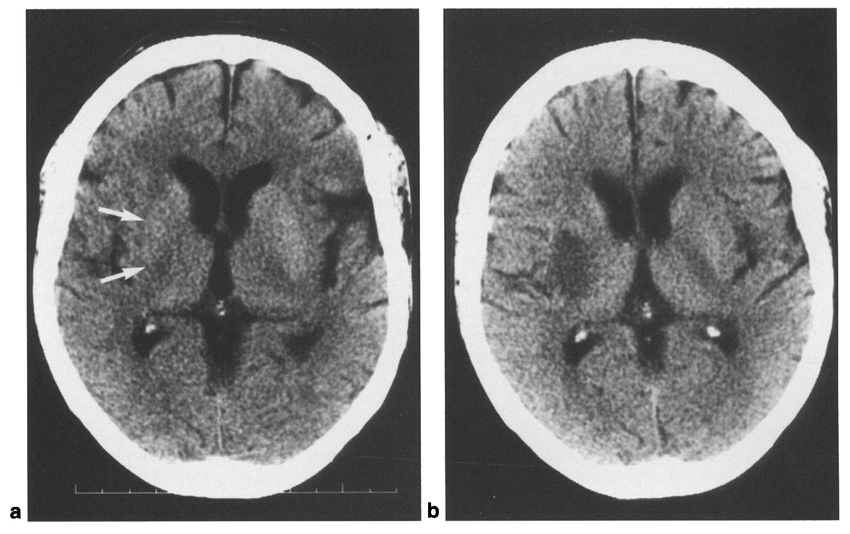

局部脑沟变浅与灰白质分界模糊

在脑梗死超急性期,患侧常出现脑肿胀,进而致使脑沟变浅。需要注意的是,不同年龄段患者的脑沟深浅存在差异,因此在判别时,对比两侧的对称性更具重要意义。阅片时,有个小技巧,适当调窄窗位和窗宽,能提高组织密度对比度,有助于更清晰地观察灰白质分界。